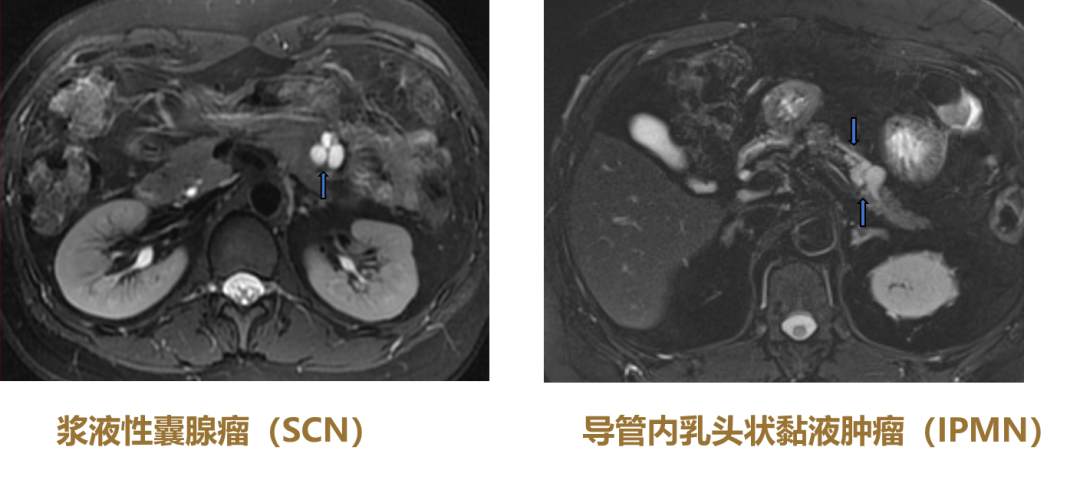

3.蜂窝征

对浆液性囊腺瘤(SCN)非常重要。微囊型SCN(全病灶蜂窝征+中心钙化+快进快出);胰腺癌-病灶内蜂窝征,必须看T2WI!

图12 微囊型SCN

(图片来源:余日胜教授讲课使用)

4.囊外囊征

单发薄壁囊外小囊多为寡囊型SCN,T2WI显示最清晰;单发厚壁囊外小囊多为黏液性囊腺瘤(MCN)。

6.花瓣征

图13 鉴别要点:无胰管扩张的花瓣征多为SCN;下游胰管扩张的花瓣征为IPMN

7.葡萄征

SCN和导管内乳头状黏液肿瘤(IPMN)的鉴别要点为,无胰管扩张的花瓣征多为SCN,下游胰管扩张的花瓣征为IPMN。MRCP非常重要。